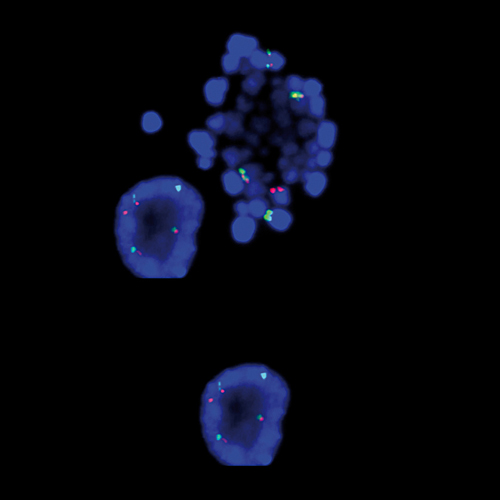

KMT2A / MLLT4 t(6;11) Fusion probe hybridized to patient material showing 47,XX,t(6;11)(q27;q23),+der(6)t(6;11) (q27;q23).

One of the relatively frequently observed translocations in AML involves the genes KMT2A and MLLT4 (previously known as AF6) at 11q23 and 6q27. The KMT2A / MLLT4 translocation results in the generation of fusion protein that retains the KMT2A N-terminus, including both an A-T hook domain and a region similar to mammalian DNA methyltransferase. The breakpoint region of the MLLT4 gene is located within intron 1 and downstream of the initiation codon. The KMT2A / MLLT4 t(6;11) Fusion FISH probe is optimized to detect translocations involving the KMT2A (previously known as MLL) and MLLT4 gene regions at 11q23 and 6q27 in a dual-color, fusion assay on metaphase/interphase spreads, blood smears and bone marrow cells.